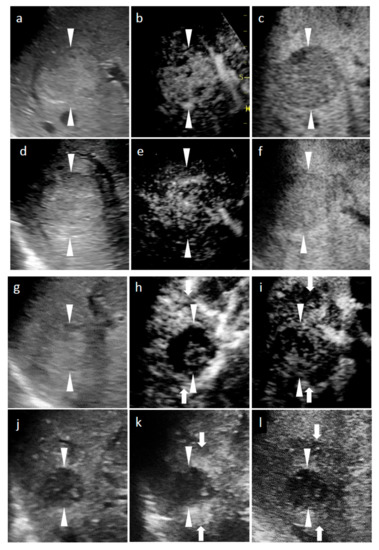

Figure 1.

Grayscale ultrasound (US) and contrast-enhanced US with Sonazoid (SCEUS) images, before and after radiotherapy (RT), for a hepatocellular carcinoma (HCC) lesion (maximum diameter: 38 mm) in segment VIII; evaluated as no local recurrence after RT. The patient was unable to undergo punctuation or surgical resection as they took two antiplatelet drugs during the subsequent 6 months of coronary stenting due to an angina attack. After RT, the patient could not receive contrast-enhanced computed tomography (CT), due to progression of chronic kidney disease. (a–c) Before RT: A hyperechoic lesion was observed using grayscale US (a). This lesion showed hypervascularity during the arterial phase (AP) of SCEUS (b) and hypoechoic (perfusion defect) during the post-vascular phase (PVP) (c). One month after RT (d–f): Grayscale US showed a hyperechoic nodule (d). This lesion showed hypervascularity during AP SCEUS (e) and appeared hypoechoic during the PVP (f) one month after RT. Grayscale US and SCEUS findings obtained after RT showed no remarkable changes, compared with those obtained before RT. Four months after RT (g–i): Grayscale US showed a hyperechoic nodule and a reduction in tumor size (g). AP SCEUS showed decreased vascularity of the HCC lesion and hypervascularity of the surrounding liver parenchyma during the arterial phase (h). Both the HCC lesion and the surrounding liver parenchyma appeared as a perfusion defect during the post-vascular phase (i). Thirteen months after RT (j–l): Grayscale US showed a hypoechoic nodule and a marked reduction in tumor size (j). AP SCEUS showed a disappearance of vascularity of the HCC lesion and slight hypervascularity of the surrounding liver parenchyma (k). Both the HCC lesion and the surrounding liver parenchyma appeared as perfusion defect during the PVP (l). Compared with four months after RT, the size of perfusion defect decreased apparently. Arrowheads indicate the margins of the HCC lesion. Arrows show the margins of irradiated surrounding liver parenchyma.

Figure 2.

Grayscale ultrasound (US), contrast-enhanced US with Sonazoid (SCEUS), and contrast-enhanced MRI (CEMRI) images before and seven months after radiotherapy (RT) for a HCC lesion (maximum diameter: 22 mm) in segment IV, evaluated as no local recurrence after RT. A safe punctuation was difficult, as the lesion was located behind the gallbladder. The patient refused surgical resection, so they received RT. SCEUS before RT (a–c): A hypoechoic lesion was observed using grayscale US (a). This lesion showed hypervascularity during the arterial phase (AP) of SCEUS (b) and hypoechoic (perfusion defect) during the post vascular phase (PVP) (c). SCEUS seven months after RT (d–g): Grayscale US showed a hypoechoic nodule and a reduction in tumor size (d). AP SCEUS showed a disappearance of vascularity of the HCC lesion and hypervascularity of the surrounding liver parenchyma (e). Both the HCC lesion and the surrounding liver parenchyma appeared as a perfusion defect during the PVP (f). After re-injection of Sonazoid during the PVP, the HCC showed hypovascularity and the surrounding liver parenchyma showed hypervascularity (g). AP CEMRI before (h) and seven months (i) after RT: Before RT, this lesion showed hyperintensity during AP CEMRI (h). Both the HCC lesion and the surrounding liver parenchyma appeared as hyperintensity at seven months after RT (i). Seven months after RT, we observed a discrepancy between the vascularity shown by SCEUS and that by CEMRI, but the lesion has not recurred for more than 3 years, suggesting that the SCEUS findings might be correct. Arrowheads show the margins of the HCC lesion. Arrows show the margins of irradiated surrounding liver parenchyma.